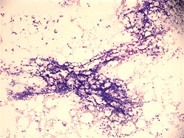

A 4-year-old girl with a known history of methylmalonic acidemia (MMA) complicated by acquired hypothyroidism, failure to thrive, and developmental delay developed pancytopenia during an admission for emesis and metabolic acidosis. She had no symptoms of a viral infection, and her cytopenias worsened over 3 weeks despite resolution of her acidosis. Her complete blood count showed a total white blood cell count of 3.1 × 10 9/L with an absolute neutrophil count of 510 /μL, hemoglobin of 6.8 g/dL, and platelets of 24 × 10 9/L. Given the long duration and unusual severity of the cytopenias, evolving aplastic anemia was considered, and a bone marrow aspirate and biopsy were performed. These showed trilineage hypoplasia and prominent dysplasia (see inset panel, arrows), including multiple vacuolated myeloid precursors (see large panel, arrows). Testing for underlying viral causes by serology and polymerase chain reaction was negative, as was testing for inherited bone marrow failure syndromes and myelodysplastic syndrome/leukemia. Her peripheral counts recovered spontaneously and fully over the ensuing 4 weeks. Interestingly, she was found to have recurrence of cytopenias on subsequent admissions for MMA-associated metabolic crises, correlating with the level of acidosis.Patients with MMA and other organic acidemias can develop bone marrow hypoplasia and trilineage dysplasia during metabolic crises, a phenomenon that has been described in a few case reports in the older literature. Cytopenias tend to correlate with organic acid levels in the blood, and count recovery typically occurs within 2 weeks, after normalization of the metabolic state. No specific treatment is needed outside of supportive care.